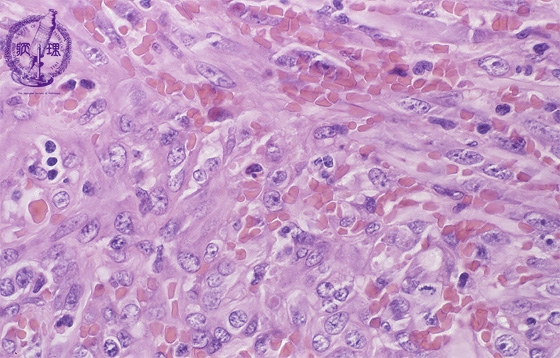

- 18.Soft tissue

- (9)Kaposi sarcoma

Microscopic findings (H.E. high power view): Spindle tumor cells detected in irregular vascular channels surrounded by swollen atypical endothelial cells, like angiosarcoma. Mitotic figures (circle) are frequently detected.

Click the image to see the enlarged image.